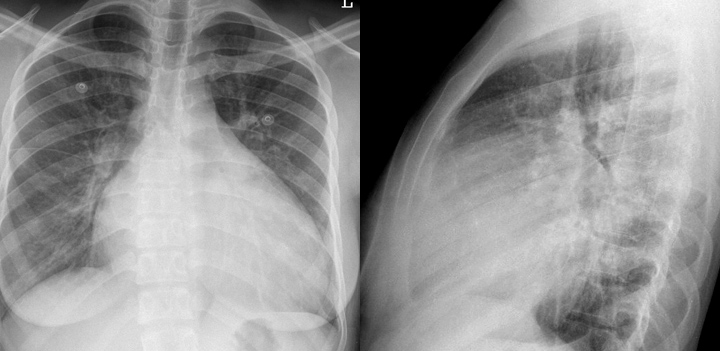

Cardiomyopathy2